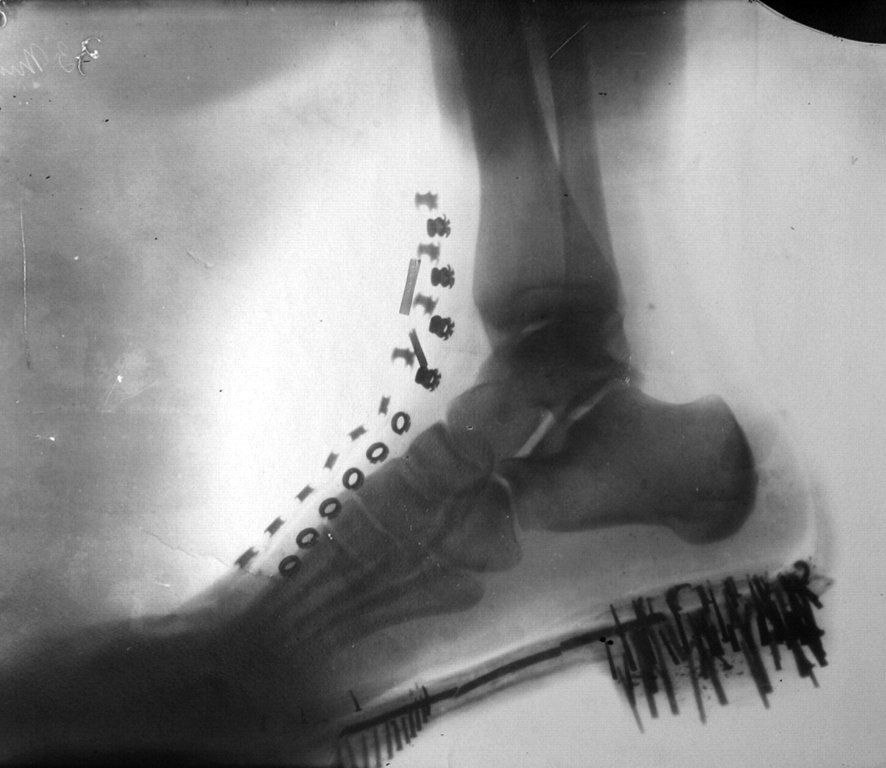

Рентгеновский снимок стопы Теслы, который он сделал в 1896 году, на следующий год после первого снимка Рентгена.